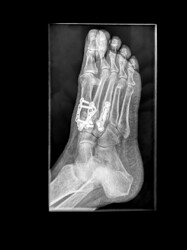

We have at least six months to go until normal “transmission” is resumed, and we can’t wait to fire off some alarms at airports in 2026!